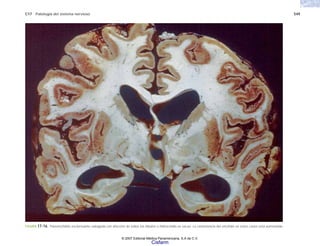

LA PATOLOGÍA EN LOS ALBORES

distintas formas, por ejemplo fiebre, vómitos de sangre,